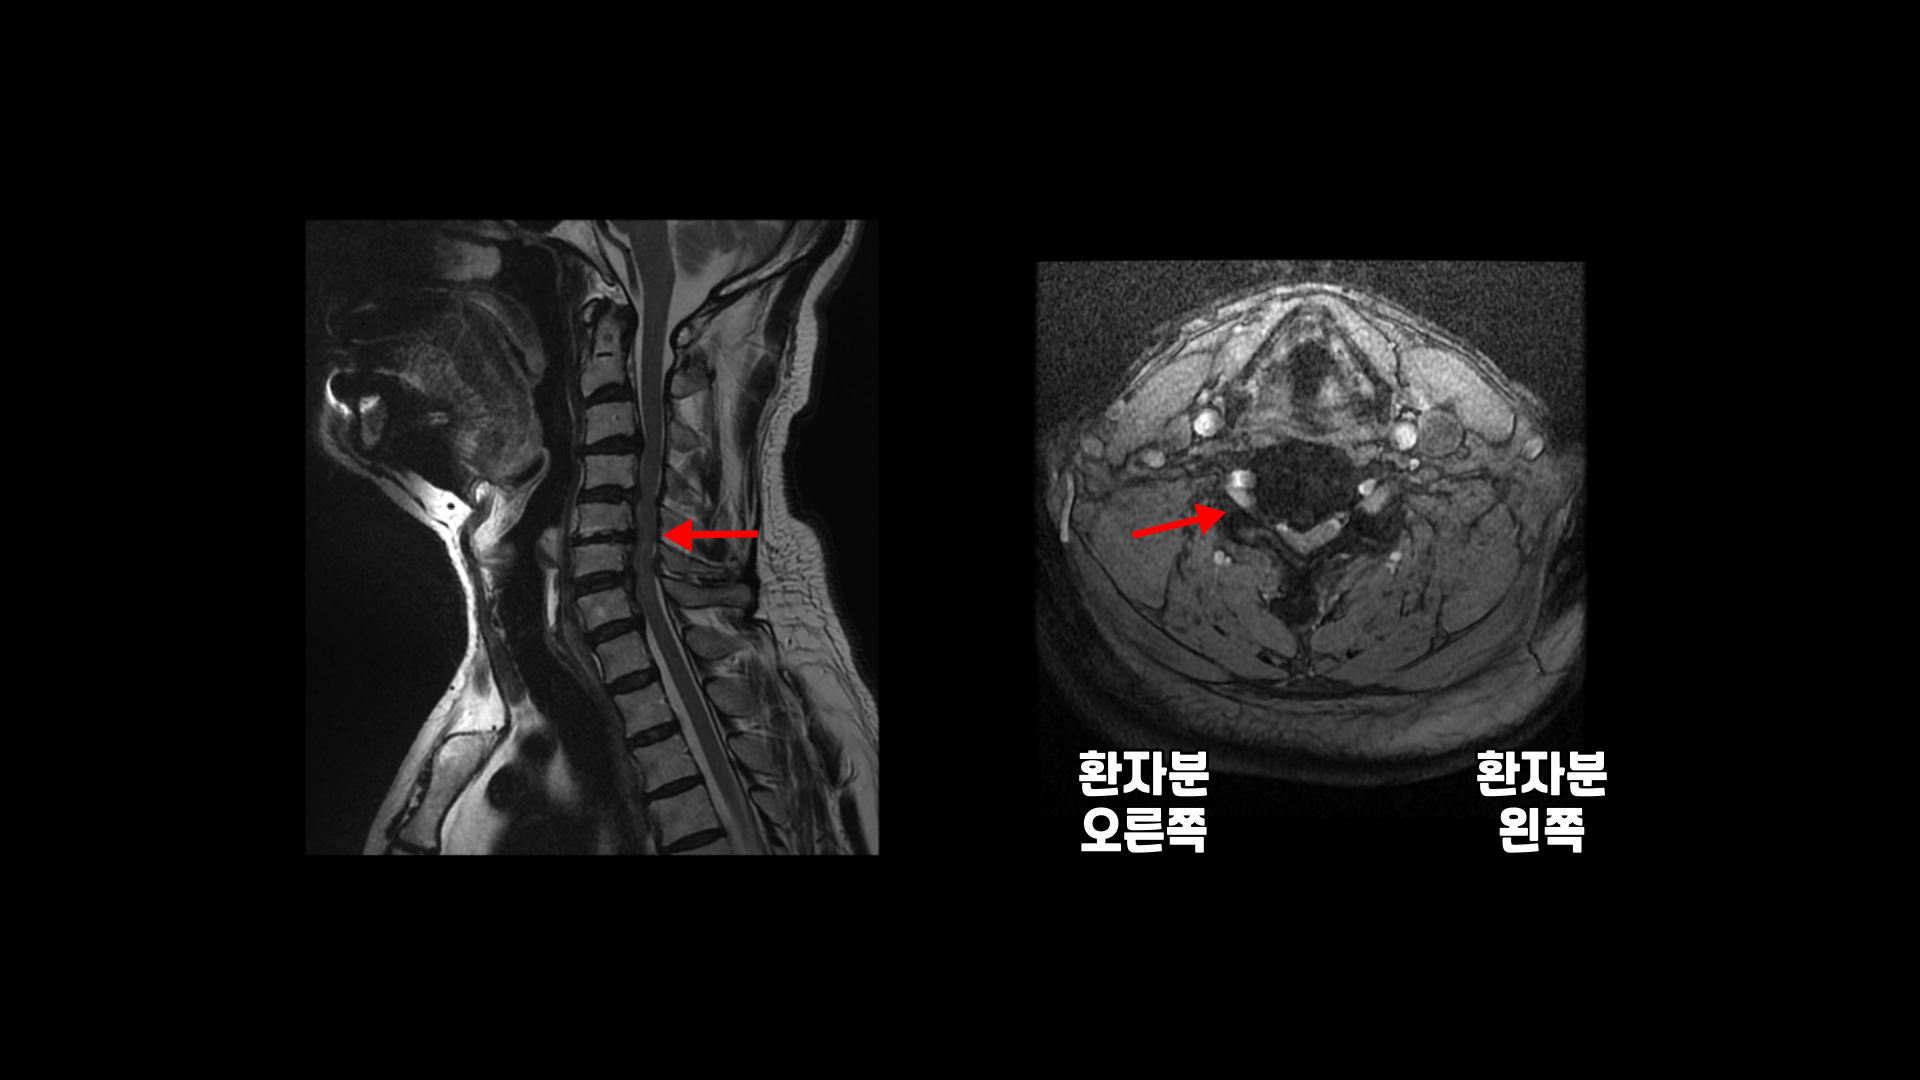

이분 MRI에서 보시다시피 전체적으로 목의 한마디만 제외하고 여러 마디가 다 안 좋습니다.

목의 3번 4번과 4번 5번에는 가운데 쪽으로 디스크 돌출이 있고

5번 6번 문제가 제일 심각한데, 가운데 우측으로 목디스크 파열이 심하게 있습니다.

오른쪽으로 보시다시피 신경 나가는 길이 디스크와 협착으로 많이 막혀 있고 척수 신경에는 경추척수증, 즉 척수신경의 손상이 보입니다.

6번 7번과 7번 흉추 1번 디스크도 가운데로 밀려 나와있습니다.